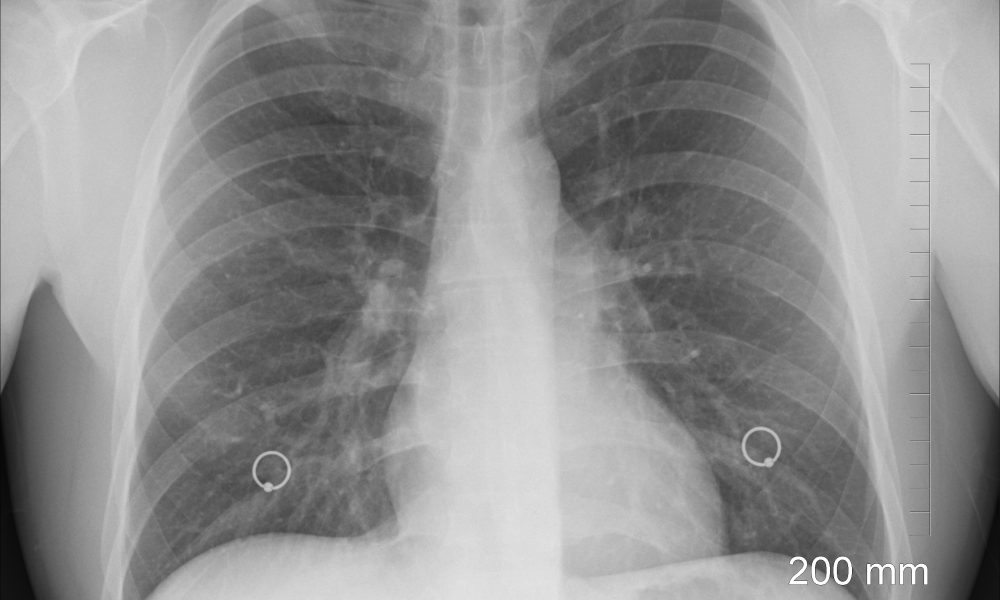

Farmer’s lung – A disease from the fields

What is Farmer’s Lung? Farmer’s lung is a condition that is caused by an allergic reaction to the mold that is found in certain crops. While the farmers are prone to expose themselves to dust from hay, corn, grass, grain, and tobacco, they are more likely to inhale them in higher concentrations. But, this doesn’t…